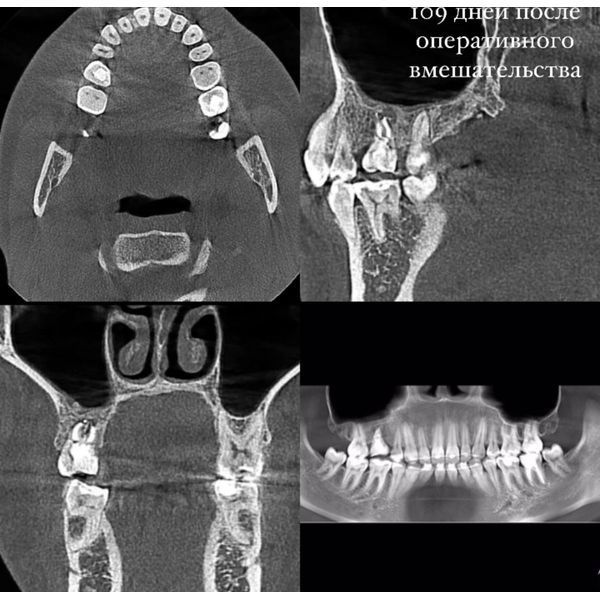

На третьем посещении корневые каналы повторно обработали и заполнили их постоянным пломбировочным материалом, после чего покрыли зуб временной пломбой. Ещё спустя 2 недели девушке поставили постоянную пломбу.

По прошествии месяца зуб препарировали — подготовили к установке безметалловой коронки, которую изготовили и поставили через 10 дней после препарирования.

В первую неделю после установки коронки пациентка каждый день приходила на осмотр, в течение последующих двух месяцев — раз в 3 дня.

Через 7 месяцев коронку покрыли керамической реставрацией. Спустя год реимплантированный зуб не вызывал новых жалоб, со своими функциями справлялся.